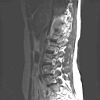

CWZ